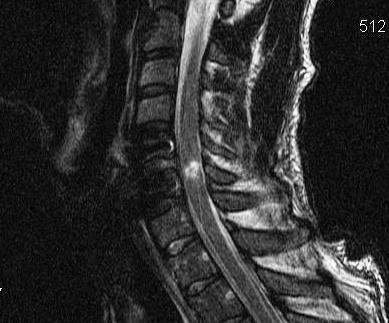

MRI

Look for herniated disc

- ? large disc could worsen neurology with skull traction / closed reduction

- ? indication for anterior approach / discetomy / fusion

Herniated disc on MRI seen after facet joint dislocation

MRI post reduction and ACDF demonstrating spinal cord injury